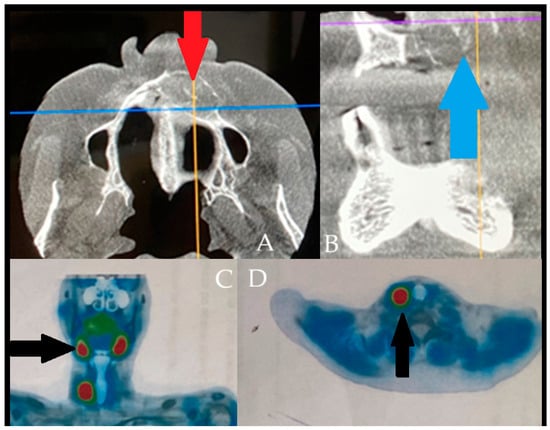

The panoramic radiograph revealed osteolytic areas, some of which were multilocular, in the left mandibular region without clear borders or shape ((A), L-left side). The residual roots of teeth 37 and 36 displayed a “floating teeth” appearance. A large radiolucent area extending toward the mandibular angle was observed, along with unilocular lesions extending anteriorly to the midline. The lesions resulted in thinning and erosion of the cortical bone. This radiographic appearance closely resembled that of ameloblastoma, central giant cell granuloma (CGCG), primary intraosseous carcinoma (PIOSC), plasmacytoma, or other malignant and non-malignant bone pathologies, including the rare possibility of malignant oncocytoma. Atypical in this case was the radiological and clinical presentation closely mimicking aggressive odontogenic or malignant lesions, despite the final diagnosis of a Brown Tumor (BT) associated with SHP [1,2,3]. Cone-beam computed tomography (CBCT) images demonstrated cortical expansion with marked thinning and bone loss (thin green arrows). Although no pathological fracture was identified (B,C), the patient reported discomfort while chewing and eating. Internal septa were evident, producing radiological patterns resembling “honeycomb” or “soap bubble” structures along with some calcified bodies in the lesion. The CBCT revealed an intraosseous lesion, measuring approximately 17 × 14 × 18 mm, that extended from teeth 33–36 toward the ramus, with irregular borders, buccal and lingual cortical perforation, irregular bone loss, and involvement of the mandibular canal. Despite this involvement, no lower lip numbness (Vincent’s sign) was present. The lesions exhibited irregular borders, and differential diagnoses also included traumatic bone cyst, Langerhans cell histiocytosis, plasmacytoma, and brown tumor (BT), primarily because of the extent of bone loss, irregular borders, bone structure changes, and a mixed radiolucent/radiopaque atypical structure on CBCT [2,4,5]. Improved diagnostics included whole-body scintigraphy and SPECT images after intravenous administration of 20 mCi Tc-99m MDP. The images showed diffuse increased uptake in the calvarium, the left hemimandible, and several ribs, most prominently at the anterior end of the right seventh rib (D). On the other hand, the scope of 3D-CBCT mandible reconstruction identified significant mandible cortical bone loss and an appearance like “moth-eaten” ((E), thick green arrows). The lesion’s radiological and clinical appearance was highly suggestive of aggressive odontogenic or malignant conditions, such as primary intraosseous squamous cell carcinoma (PIOSCC), osteosarcoma, plasmacytoma, or metastatic disease. Because of this atypical presentation, an incisional biopsy was prioritized before systemic markers were assessed, to exclude malignancy and establish a definitive histopathological diagnosis [4,5,6]. An incisional biopsy was performed under local anesthesia, and histopathological analysis revealed the presence of giant cells. Blood tests were obtained, which supported but did not definitively confirm the diagnosis (Supplementary Materials). At baseline, prior to the incisional biopsy, serum PTH (1070.6 pg/mL) and ALP (381 U/L) levels were markedly elevated, while calcium (9.3 mg/dL) and phosphorus (2.6 mg/dL) remained within or slightly below the reference range, indicating an early biochemical profile consistent with hyperparathyroidism. The patient was subsequently referred to the endocrinology and nephrology departments for further evaluation, including parathyroid function testing. Considering these findings and the patient’s systemic condition, SHP was confirmed. Medical treatment was initiated, leading to limited regression of the lesion and swelling, though complete remission was not achieved.